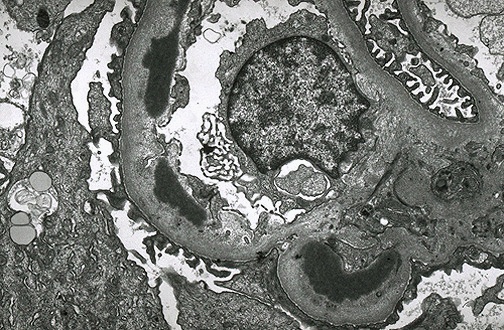

| The electron micrograph above demonstrates dense deposits in the basement membrane typical for MPGN type II. These dark electron dense deposits within the basement membrane often coalesce to form a ribbon-like mass of deposits, as seen in the electron micrograph below. |